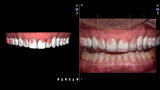

Fig. 5: DSD protocol: image of patient smiling wearing a lip and cheek retractor.